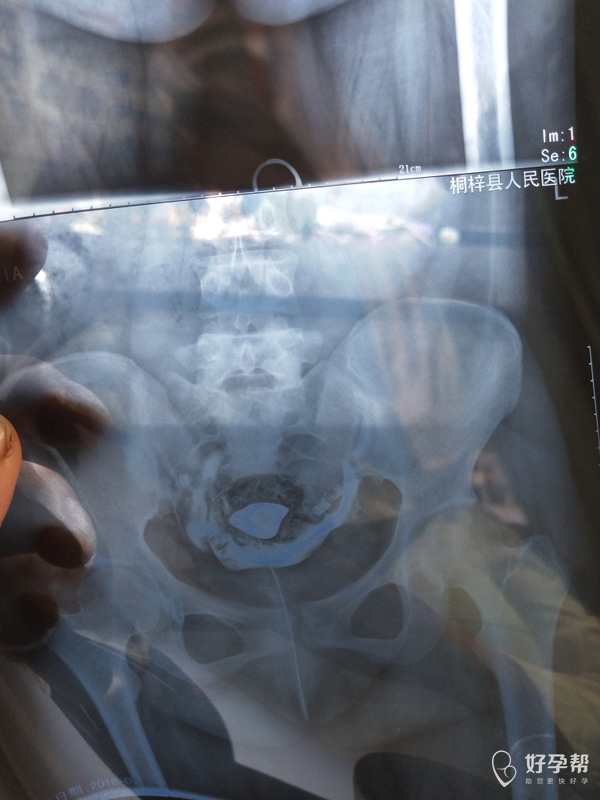

医生 看看我的输卵管造影

输卵管堵塞一是手术,二是试管婴儿。建议直接试管婴儿。